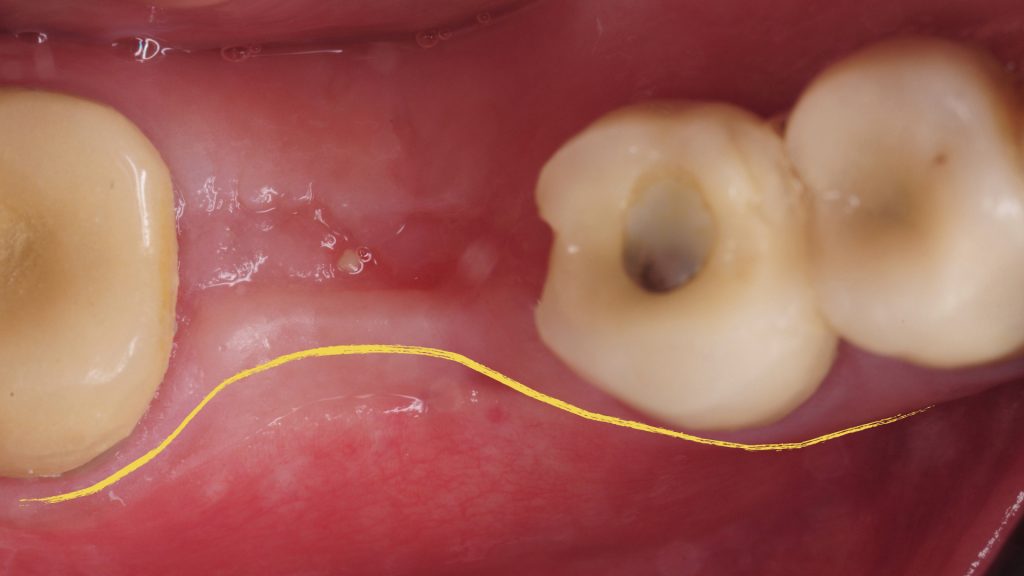

Tissue Grafting Videos

Videos related to bone and soft tissue augmentation for development of implant sites or related to correction of defects.